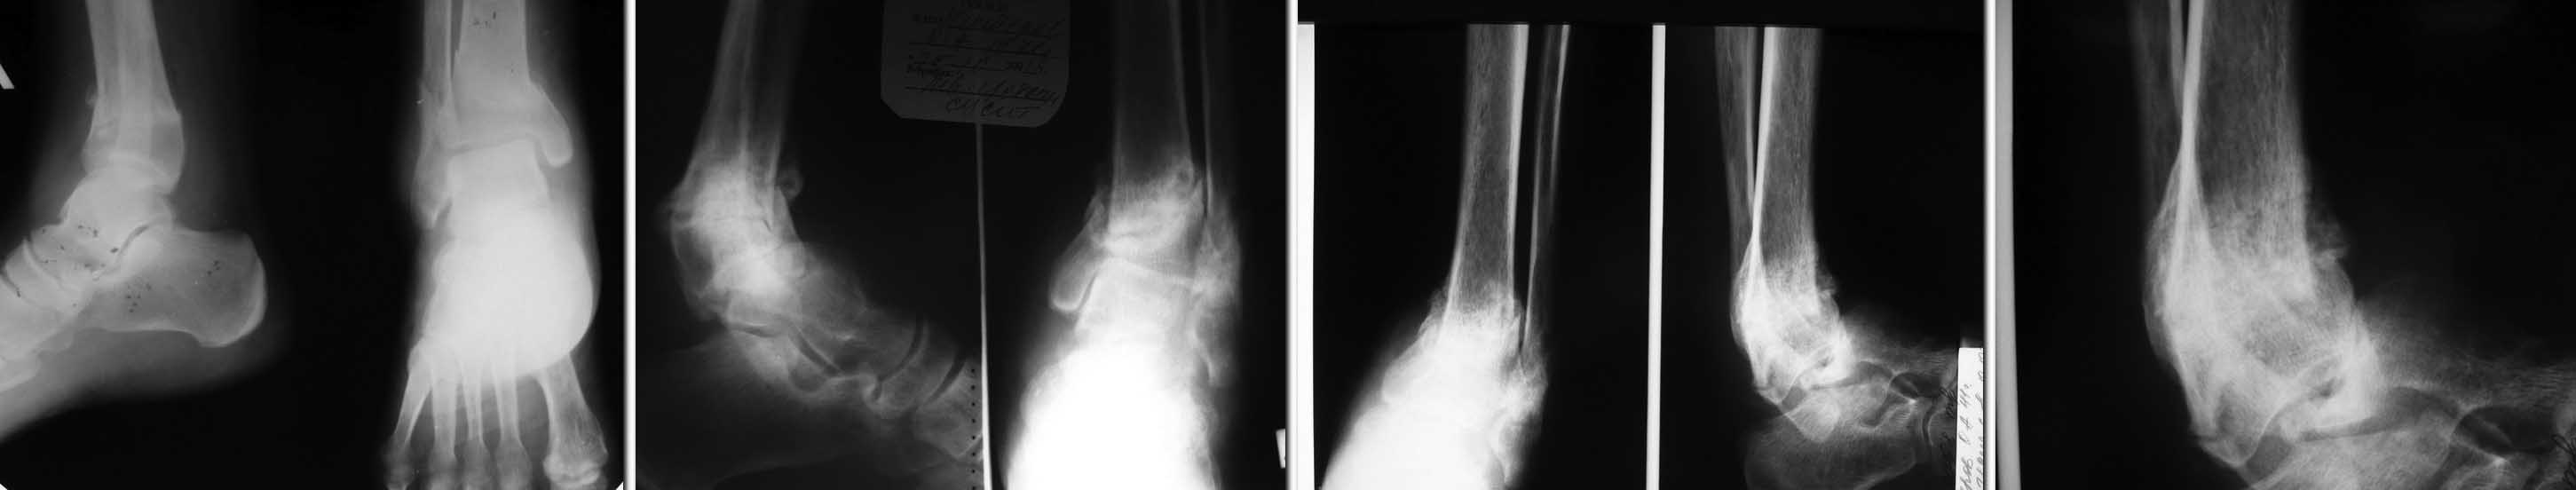

в начале лета сего года подвернул ногу. Появились умеренные боли при ходьбе, постепенно усиливались, через пару недель обратился в поликлинику к хирургу.  Выполнена р-графия (1 снимок) Выявлен перелом, рекомендовано "ходить потихоньку с тростью"  (со слов пациента). В октябре повторное обращение и контрольная р-графия из за усиления болей - выявлен ложный сустав,

(снимок 2 ) Пациент начал ходить по консультантам. К нам обратился к декабрю, боли усилились значительно. Р-логически - полный передний вывих стопы (последняя пара рентгенограмм), однако пациент ходит с тростью.